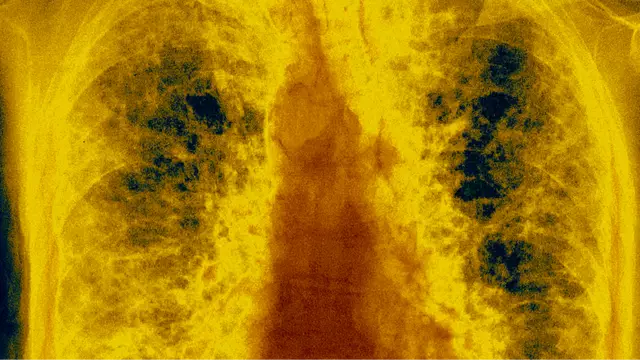

“It causes inflammation and scarring in the bronchioles (the smallest branches of the lungs), making it increasingly difficult for air to move through,” said O’Shea.

“There’s no cure for popcorn lung. Once the lungs are damaged, treatment is limited to managing symptoms.

“This can include bronchodilators, steroids, and in extreme cases, lung transplantation. For this reason, prevention – not treatment – is the best and only defence.”